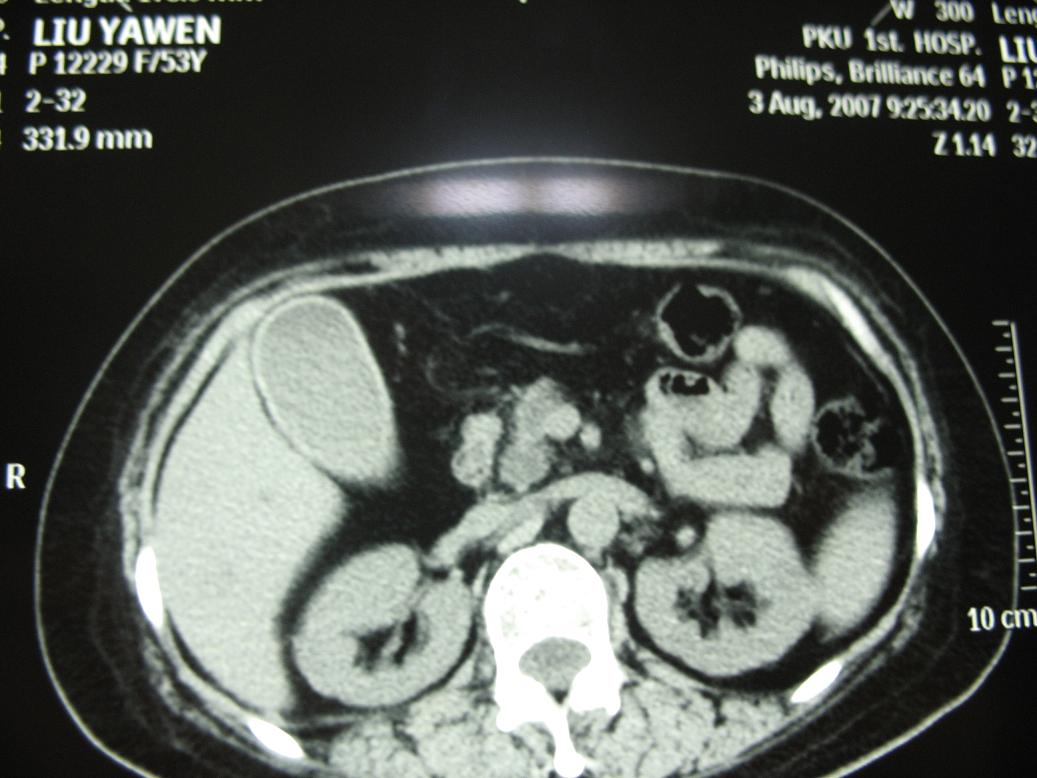

标题: CT17151:女 53岁 腹痛数月余 轻微黄疸 [打印本页]

女 53岁 腹痛数月余 轻微黄疸

1)考虑胰头癌。2)胆囊炎。

壶腹周围占位(钩突ca?)

胰腺钩突mt

支持胰腺钩突ca伴胆系梗阻,胆囊炎

考虑 胰头癌可能性大。